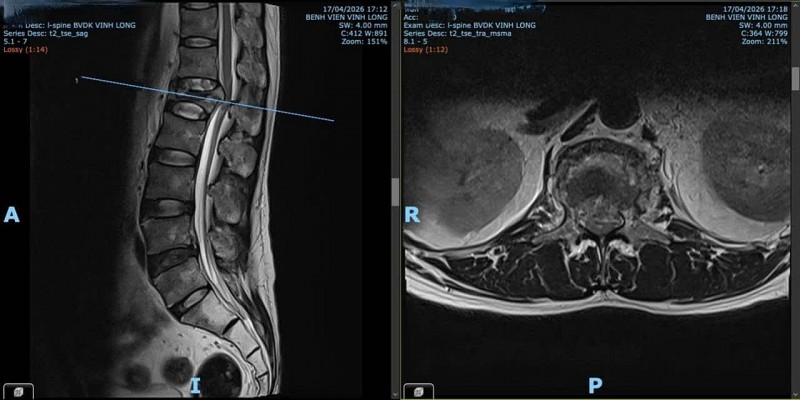

Kết quả chụp MRI cột sống thắt lưng ghi nhận xẹp đốt sống L1, mảnh gãy phía sau thân sống di lệch ra sau chèn ép bao màng cứng, gây hẹp nặng ống sống với đường kính trước sau chỉ còn khoảng 6mm. Đồng thời, X-quang khung chậu thẳng và CT vùng hông đùi trái ghi nhận hình ảnh theo dõi hoại tử chỏm xương đùi trái. Siêu âm bụng cấp cứu không ghi nhận dịch ổ bụng hay tổn thương tạng đặc.

| Hình ảnh chụp X-quang cột sống trước phẫu thuật của người bệnh |